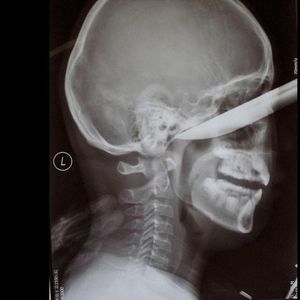

Gırtlak kanseri nedeniyle boyun ön kısmında soluk borusuna açılan delik sayesinde nefes alan Fahri Akın'ın sol akciğer girişinden nefes borusunu tıkayan 5 santimetrelik kürdan çıkarıldı.

Necmettin Erbakan Üniversitesi Meram Tıp Fakültesi Hastanesine giden Akın'ın rahat nefes alması için soluk borusuna stent yerleştirilmesine karar verildi. Stent için nefes borusu ve akciğerde inceleme yapılırken doktorların dikkati sayesinde Akın'ın sol akciğer girişinde nefes borusunu 5 santimetrelik kürdanın tıkadığı fark edildi.

Ameliyatı gerçekleştiren, Necmettin Erbakan Üniversitesi Meram Tıp Fakültesi Göğüs Cerrahisi Ana Bilim Dalı Öğretim Üyesi Prof. Dr. Tamer Altınok, ana nefes borusunda daralma düşünülen hastanın kendilerine yönlendirildiğini söyledi. Stent takılması istenen hasta için hazırlık yaptıklarını belirten Altınok, vücudunun stent için uygun olup olmadığına endoskopik yöntemle bakıldığında ana nefes borusunun içinde çeşitli kalınlaşmış dokular görüldüğünü kaydetti.